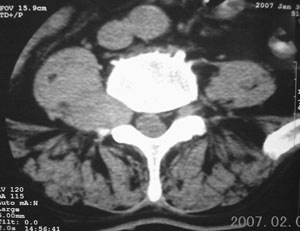

标题: CT8116:帮忙看这侧隐窝里是什么?男,75岁,腰周疼5-6年 [打印本页]

标题: CT8116:帮忙看这侧隐窝里是什么?男,75岁,腰周疼5-6年

男,75岁,腰周疼5-6年。别无症状。

右侧椎旁、侧隐窝软组织肿块,呈不规则双极征改变,椎体后外缘骨质弧形压迹,椎间孔扩大;考虑神经源性肿瘤,神经鞘瘤可能性大,需与神经纤维瘤相鉴别。

病变侧椎间孔扩大,椎体缘受压吸收;

考虑神经源性肿瘤,神经鞘瘤可能;

病变侧椎间孔扩大,椎体缘受压吸收,考虑神经源性肿瘤(神经鞘瘤可能)。